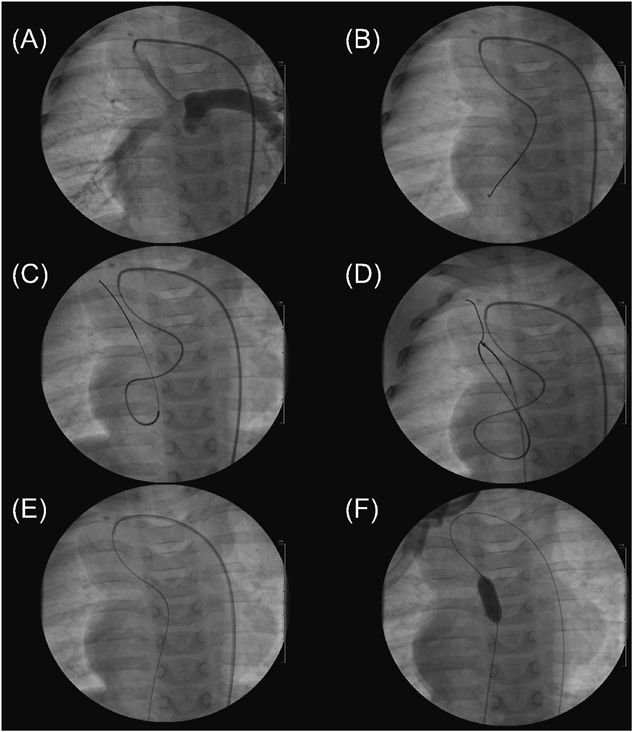

Fig. 1 FA–SPS–FV wire loop to assist BPV in Case 1

(A) A pulmonary arteriogram. (B) From the shunt, a 4-Fr catheter following a 0.035″ wire was retrogradely passed through Pin-PV into LV. (C) From the catheter, a 2.3–2.8-Fr microcatheter bent into a U shape was advanced into LV, from which a 0.016″ wire was advanced up into SVC through MV. (D) The wire was caught with a 10-mm diameter snare catheter advanced via the right FV sheath. (E) The wire was pulled out of the body, and an FA–SPS–FV wire loop was completed. (F, G) On the wire loop, a 7 mm diameter×2 cm length balloon catheter was advanced, and BPV was performed. (H) After BPV, antegrade flow through the perforated valve was recognized. (I) Pulmonary regurgitation seemed trivial.

First, a 0.035″ Radifocus guidewire and a 4-Fr Cobra-shaped Glidecath were advanced to MPA through the central shunt via the right FA sheath. We could then pass the wire through the pinhole-like pulmonary valve (Pin-PV) and followed the Glidecath into the left ventricle (LV). Through the Glidecath, a 2.3–2.8 Fr microcatheter (Prowler Select Plus, Codman), the tip of which we bent into U shape, was advanced into LV. Next, from the microcatheter, we carefully advanced a 0.016″ GT wire into the superior vena cava (SVC) through the mitral valve (MV). We caught the wire with a 10-mm diameter snare catheter, which was advanced via the right FV sheath, and pulled the wire out of the body to make an FA–SPS–FV wire loop. Third, from the FV sheath, we delivered a 7 mm diameter×2 cm length balloon catheter (Sterling, Boston Scientific) to the Pin-PV on the wire loop and inflated it to 10 atm (Fig. 1). With sufficient support by the wire, complications such as bradycardia, hypotension, mitral or pulmonary regurgitation, and atrioventricular block were not observed. After BPV, the pulmonary valve orifice diameter became 3.5 mm and her SpO2 increased from 75 to 85%.